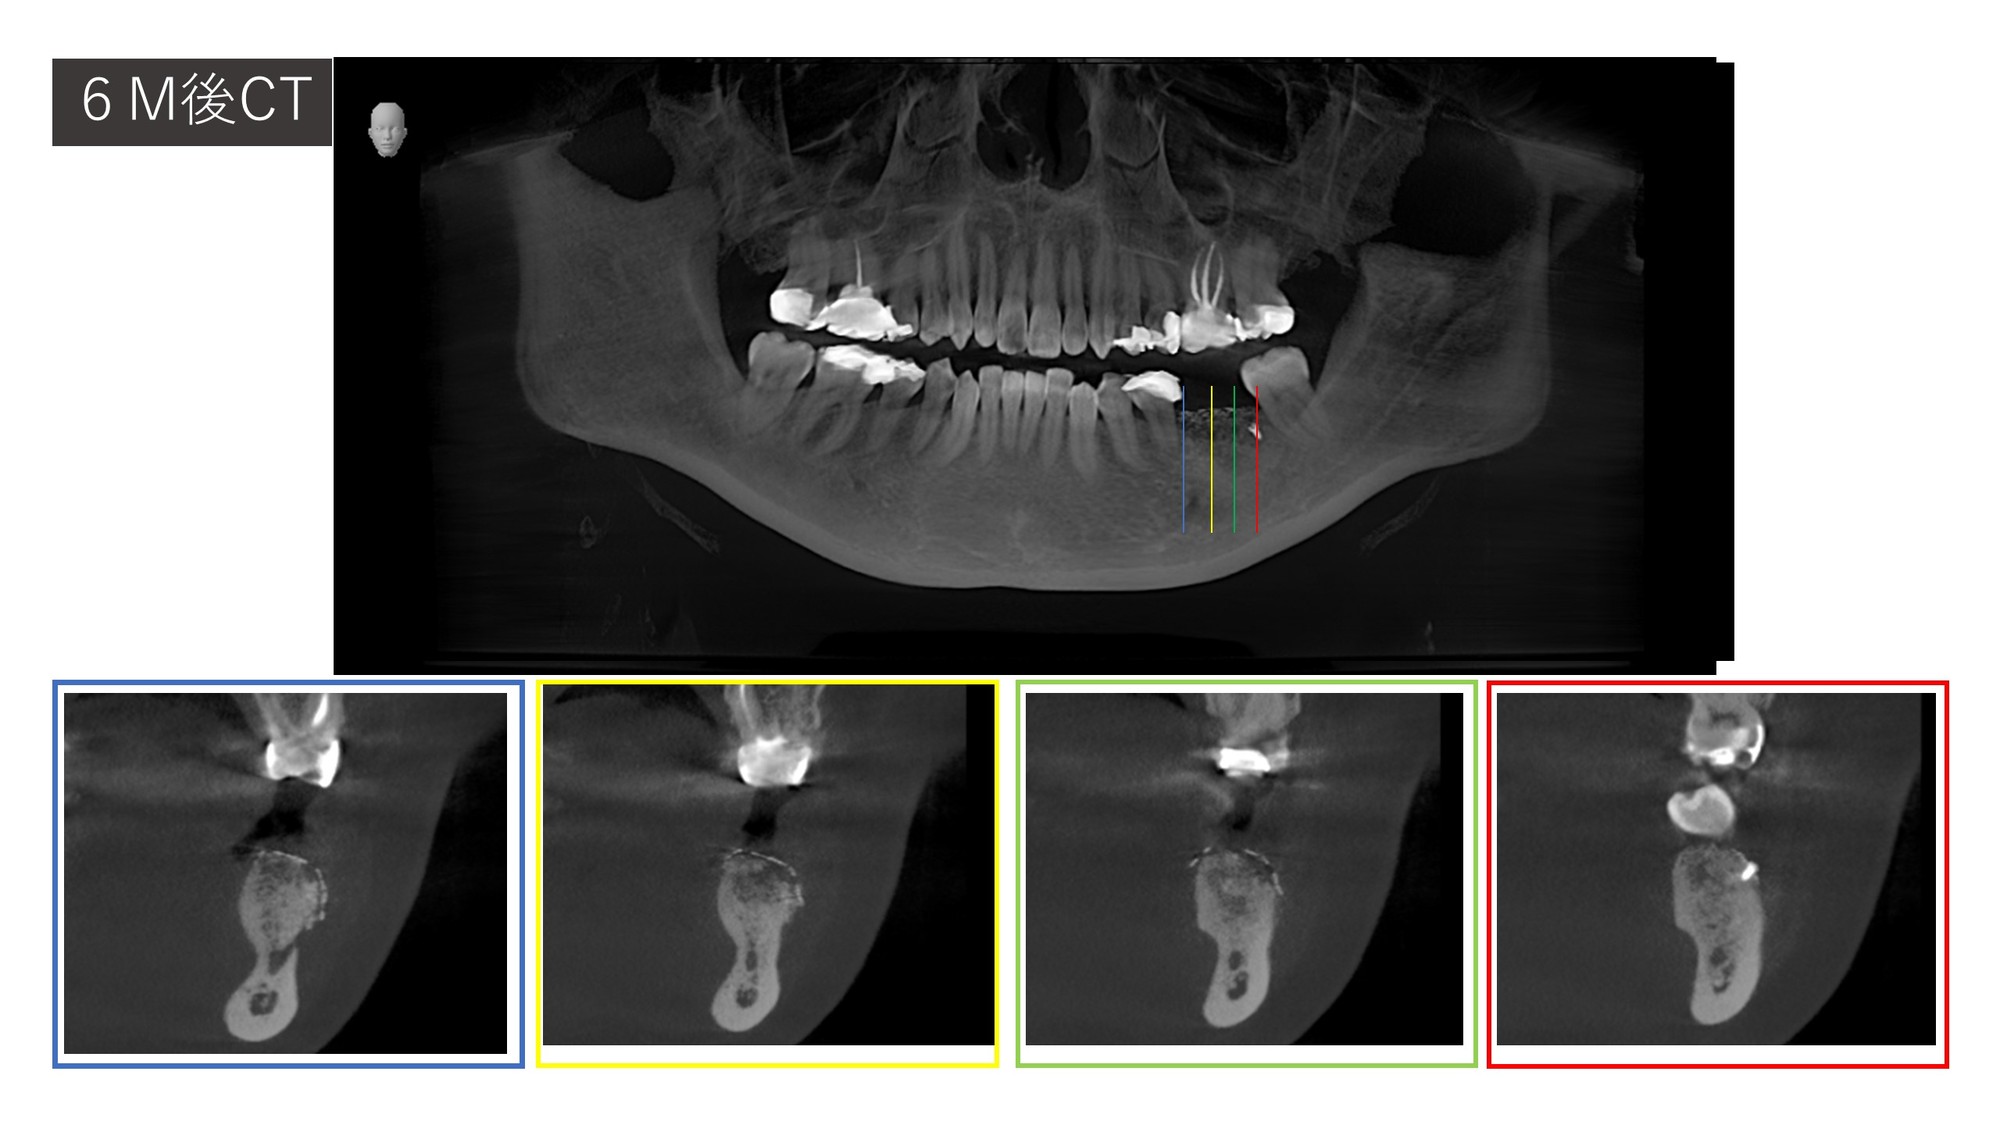

三次元的な骨吸収量と補綴的に必要な造成量を調べるために、CT撮影を行います。

骨がないですね。

しかも内側が深くえぐれているので、インプラントを埋入する深度がシビアです。

GBRオペから6か月、ほぼ計画通りに骨の形ができていることが分かります。